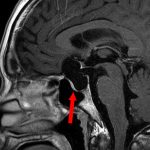

676

'25年10月

20代

脳幹部腫瘍

頭蓋内腫瘍摘出術

No.’25_78 手術前1

No.’25_78 手術前2